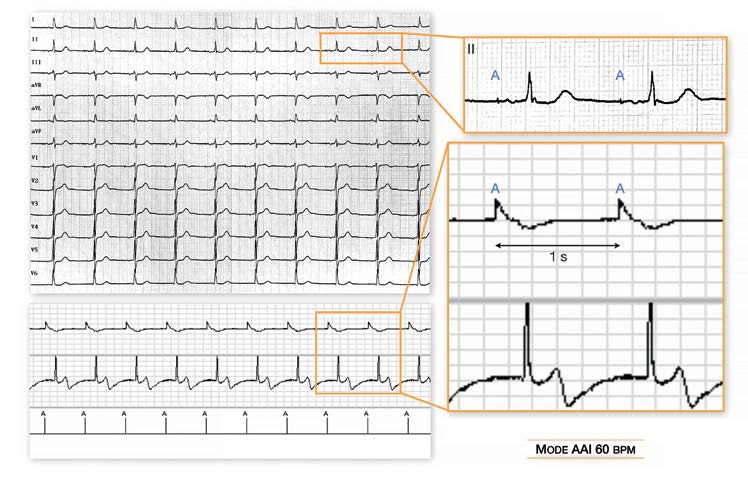

Mode AAI 60 battements/minute: stimulation atriale à la fréquence minimale (intervalle d’échappement de 1 seconde) plus rapide que l’activité sinusale spontanée; conduction atrio-ventriculaire spontanée; Tracé 8: Mode AAI 60 Battements/minute